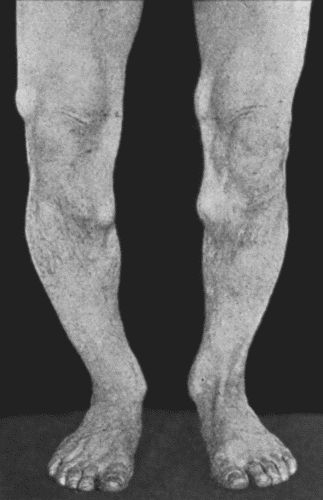

| 67. | Extensive Varix of Internal Saphena System on Left Leg | 291 |

| 164. | Charcot's Disease of both Ankles: front view | 535 |

| 165. | Charcot's Disease of both Ankles: back view | 536 |